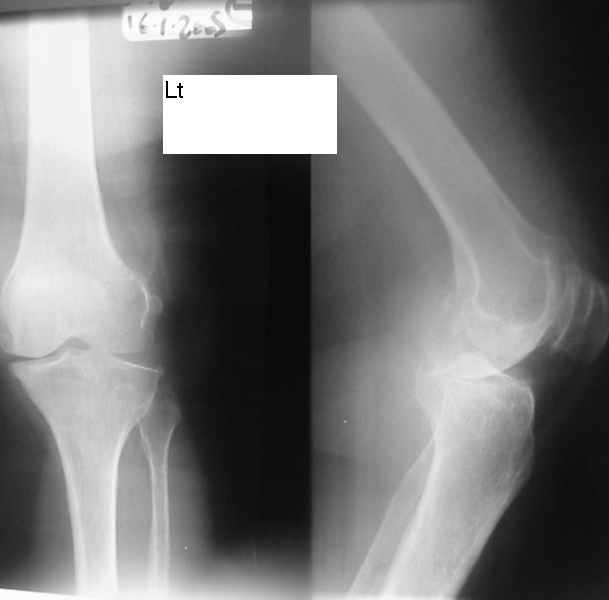

Dorogie Kollegy,Ko mne obratilas' bol'najia, ei 64 goda, ona stradaet ot dvuhstoronnego varusnogo gonoartroza, ei bila vipolnena Visokajia Ostotomjia goleny sprava 01.06.2004, zona osteotomii ne sroslas', plastina bila udalena 12.09.2004 (vidimo iz-za ee nestabilnosti), zona osteotomii tibia bila fixirovana 3-mjia shurupami. Seachas sylno bespokoyat boly v dvuh sustavah, hodit s trudom s pomoshyu Walker, a voobshe ona seachas na invalidnoi kolyaske. Podzkazite, pozhalusta, kak mozno ei pomoch' (snimky prilagayutsa)

U bol'nogo non-union osteotomii tibii. V vozraste 64 let, sdelal bi sleduiezhee:

2. Ne sovetuiu delat' geroicheskix postumkov v otnoshenii Non union. Tut est' mnogo problem, ved' esteotomia provedena ne pravili'no s tochki zrenia deformazii. Orientazia ploskosto kollennogo sustava xotia ne ploxa v sagital'noii ploskosti, no vo frontl'noi idet sil;noie otklonenie narozhu i vniz. A nam tida ne nado.